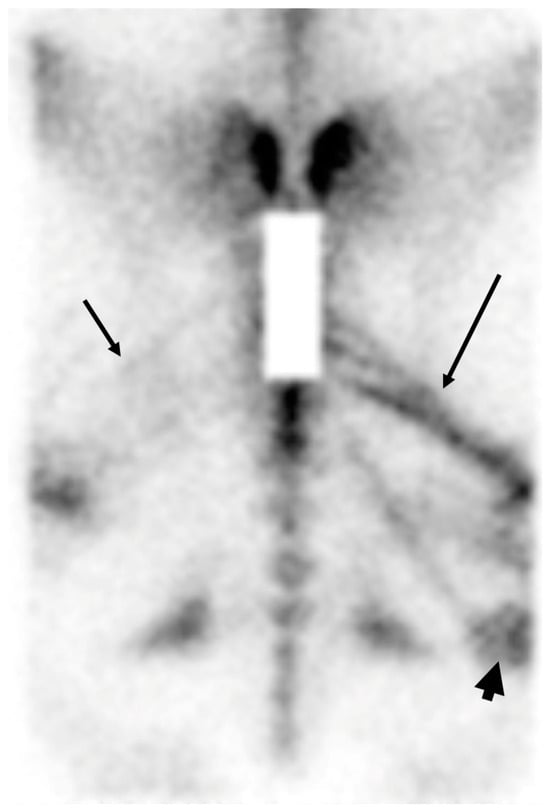

2.3. Whole Body Imaging for Multiple Limb Lameness or Poor Performance

3.1. Imaging of Vertebral Column, Ribs and Proximal Limbs